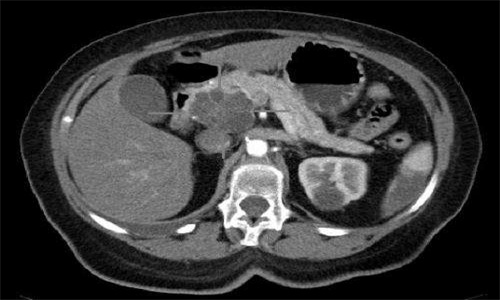

医学研究人员推测,激活髓细胞的两种治疗方法的组合可能有效地治疗抵抗传统免疫疗法的难治性胰腺癌。动员免疫系统摧毁癌症是过去十年的突破性治疗方法之一,通过免疫疗法动员T细胞发动对恶性肿瘤的战争,促进了癌症的击败。肿瘤学家和他们的病人面临的问题是,基于T细胞的免疫疗法对一些癌症有效,但不是所有形式的疾病。

科学家们现在说,活化的T细胞是免疫疗法中非凡的杀手,虽然这些淋巴细胞在动员起来对抗一些癌症时是有效的,但显然有新策略的作用。一组癌症生物学家正在研究一种激活骨髓细胞抗肿瘤的方法,他们表示,在治疗一种耐药形式的胰腺癌方面,他们看到了积极的结果。

宾夕法尼亚大学的新研究正在调查一种不同类型的免疫疗法的潜力,这种实验方法依赖于两种针对骨髓细胞的免疫疗法。

这种策略的研究正在动物模型研究和早期人类临床试验中进行。指导动物模型和人类研究的基本概念取决于一个看似简单的概念:结合两种激活髓样细胞的治疗方法可能会成功对抗肿瘤,而传统的基于T细胞的免疫疗法则失败了。